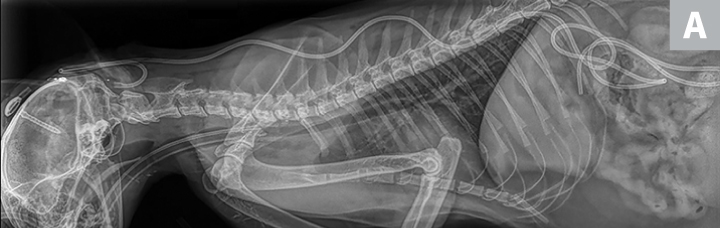

X-ray and CT images of a cat showing radiopaque ventriculoperitoneal shunt in place within skull.

FIGURE 5

(A) Postoperative lateral radiograph and (B) transverse CT image showing a ventriculoperitoneal shunt placed in a cat. Although the well was not flush with the skull, the shunt appeared stable after the sutures were tightened. The cat did well after surgery. Images courtesy of Dr. Eric Glass, Red Bank Veterinary Hospital/Compassion First Pet Hospitals